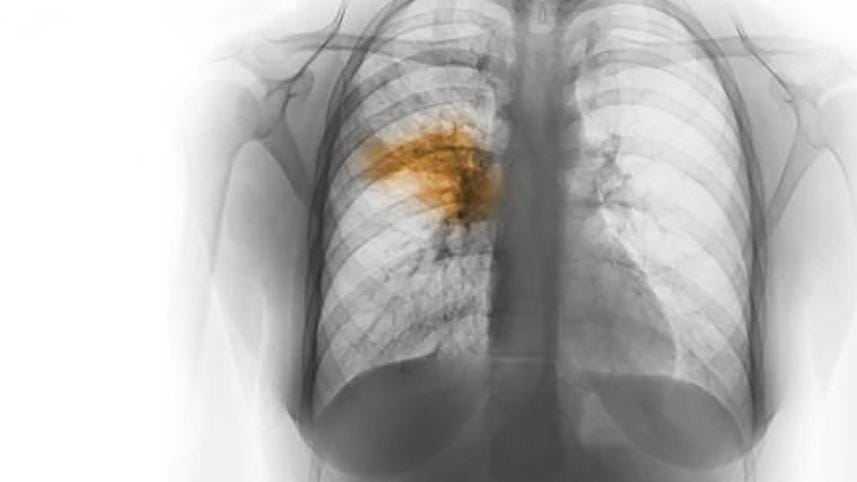

Fifteen children died of pneumonia at hospitals in Khagrachhari, Rangamati and Bandarban in the last two weeks, said doctors.